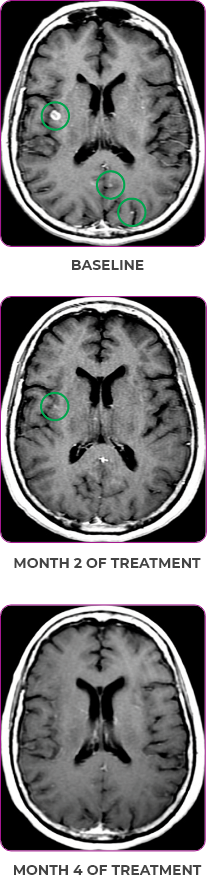

PATIENT CASE:

METASTATIC NSCLC1,a

- 30-year-old female

- Progression on first-line doublet chemotherapy

- PRa after 6 weeks of treatment with VITRAKVI® (larotrectinib)

- Complete clinical response achieved by 12 months with residual scarring

Response to VITRAKVI1

- Partial response and symptom improvement confirmed by chest X-rays after <1 month of treatment

- Imaging performed 6 weeks into treatment revealed considerable decrease in the size of both target lesions

- Patient was symptom free and remained on VITRAKVI

Response in primary and metastatic lesions1

Lung imaging of primary tumors.

SCAN 1: LUNG

SCAN 2: LUNG AND BONE